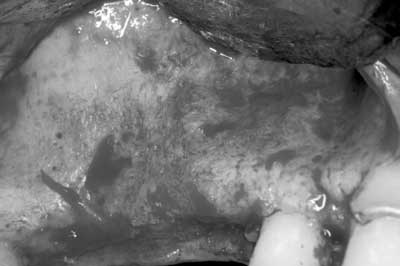

1. A full-thickness flap is reflected to gain access to the lateral wall of the maxillary sinus (Fig. 1). In this area the bone is normally very thin, usually less than 1 mm.Fig. 34. The sinus membrane is separated from the bony wall. Perforations of the membrane occur frequently during this phase. To increase safety and reduce complications, the air-driven sonic handpiece is used, coupled with the discoid insert. The insert is activated (vibrating and irrigated by the water spray) and then placed between the lateral bone wall and the Schneiderian membrane (Fig. 4).